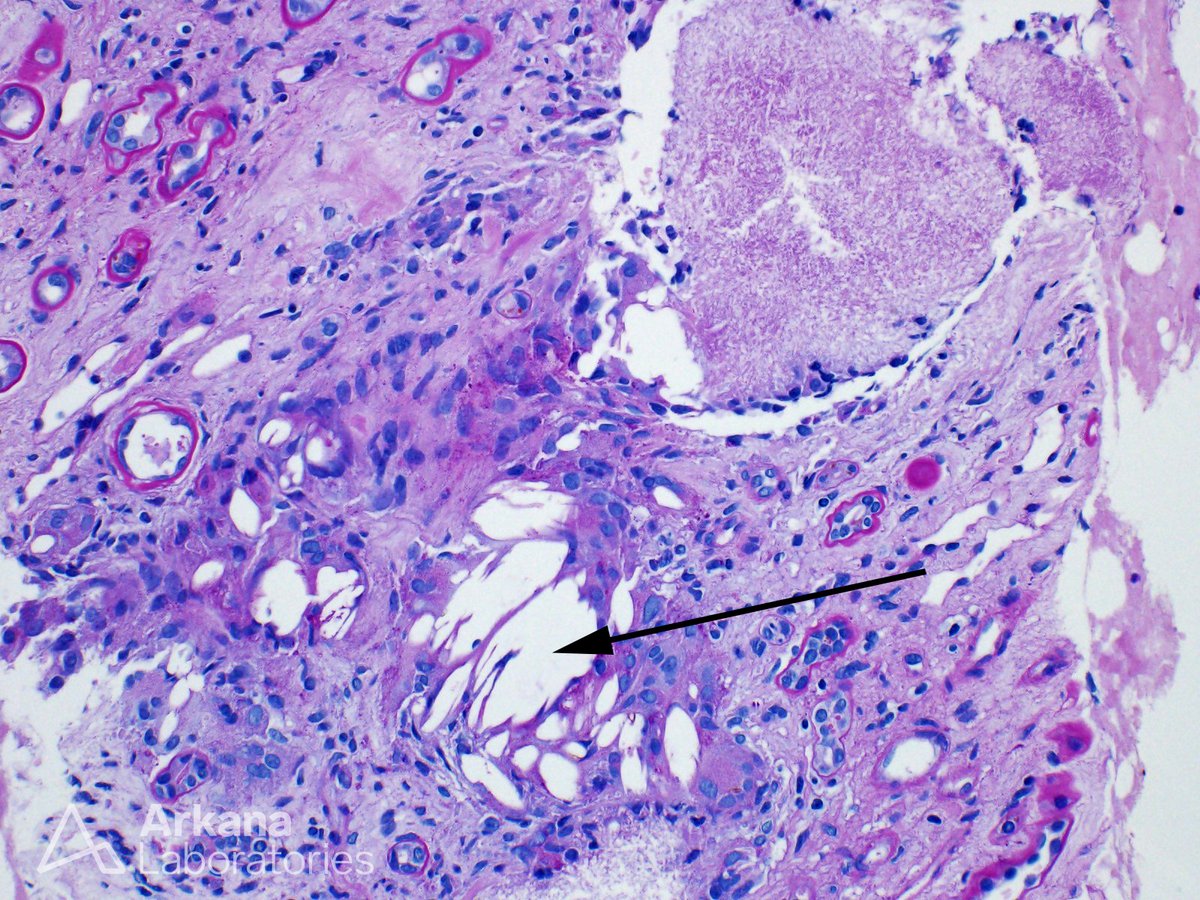

This biopsy shows the characteristic features of uric acid nephropathy (commonly known as gout), which results from precipitation of uric acid in the kidney parenchyma. Tophi frequently occur in the medulla, and usually consist of central regions of acellular, granular material